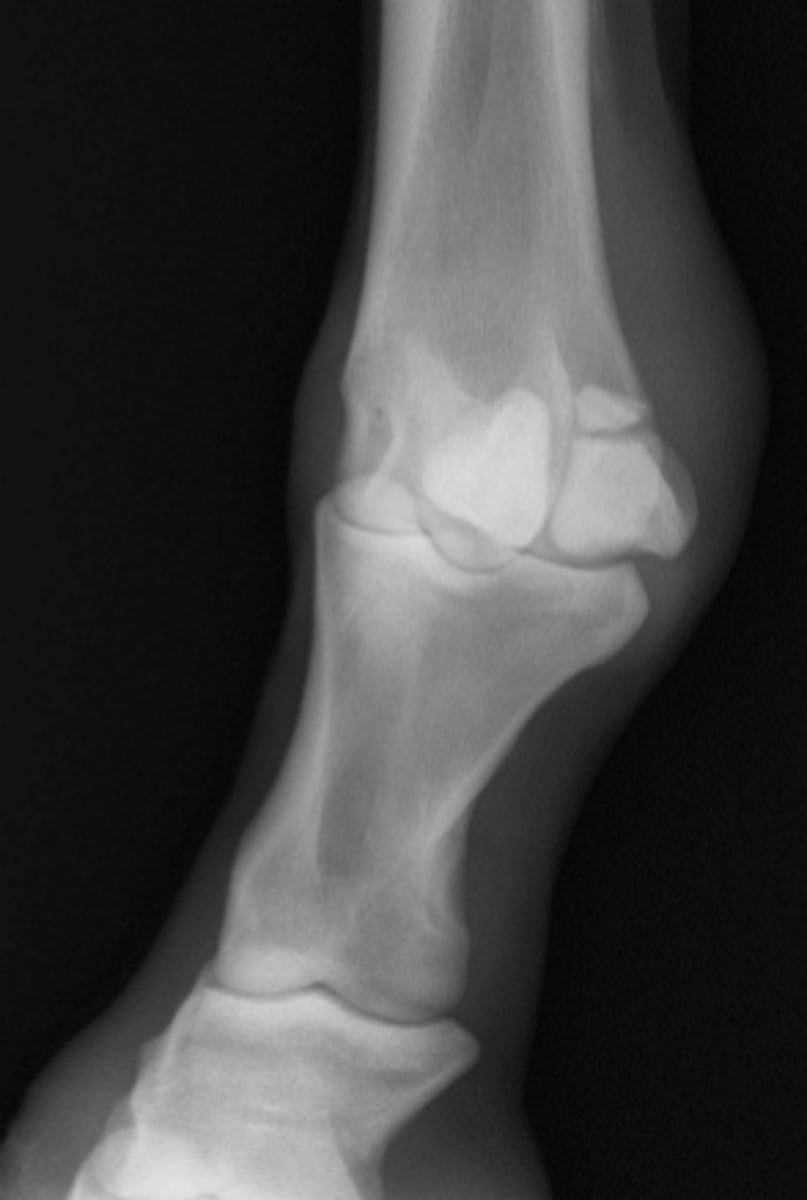

Osteochondral fragment

What is the radiology term for this lesion?

Arthroscopy

What is the preferred treatment for this lesion?